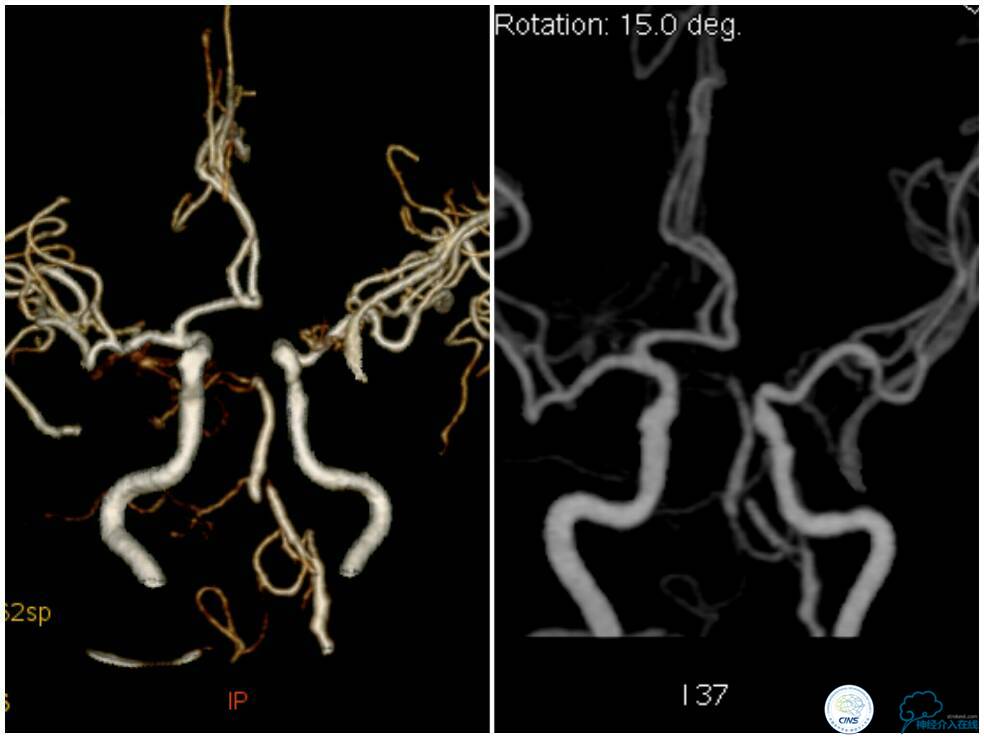

支架释放过程中给予替罗非班3 ml/h静脉持续泵入,以预防急性血栓形成。最后一枚支架释放完毕后造影显示右椎动脉V4段再通,支架贴壁良好,前向血流TICI分级3级,左椎动脉V4段逆向显影(箭头)(图11)。